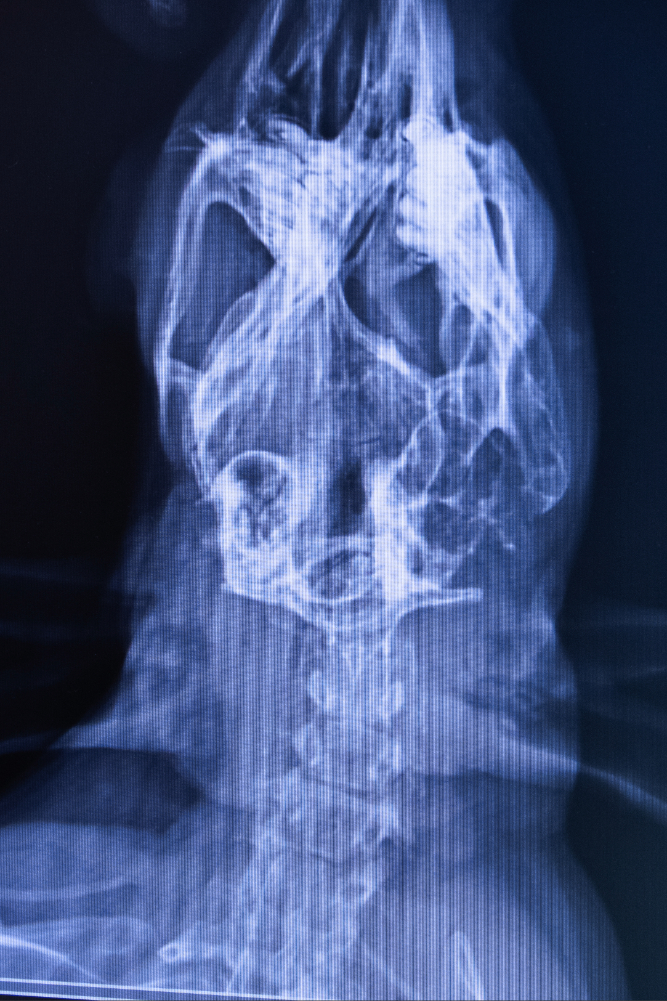

Jeannot est un lapin bélier âgé de 6 ans. Soudainement, il s’est mis à refuser de manger et, symptôme impressionnant, à perdre l’équilibre. Sa maîtresse a dès lors décidé de s’orienter vers une vétérinaire NAC. La radio était sans appel: otite de l’oreille moyenne. La bulle tympanique, quant à elle, était également touchée.

Sa vétérinaire nous explique l’alternative proposée et acceptée par sa propriétaire : remplacer le scanner par une radio qui elle, ne coûte qu’une centaine d’euros. Moins cher mais moins précis, et moins sûr donc.

par une otite de l’oreille moyenne. Cabinet vétérinaire du Docteur Balzat. Retinne, le 13/05/25